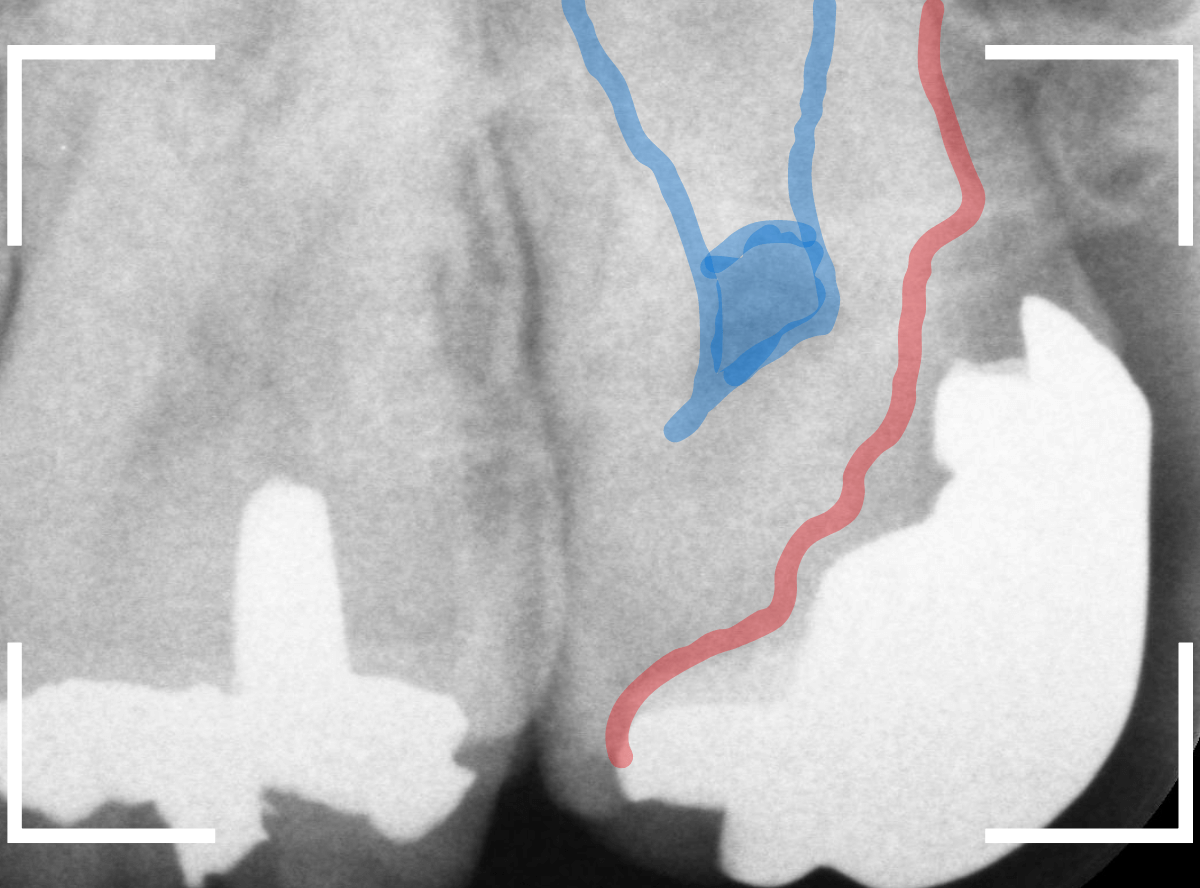

やはり、奥歯の端が大きな虫歯になっています。

青いラインが歯の神経、赤いラインが虫歯です。

レントゲン写真上では虫歯が神経まで達しているように見えます。

これは、神経を取らないとダメかもしれません。

レントゲン写真で確認します。